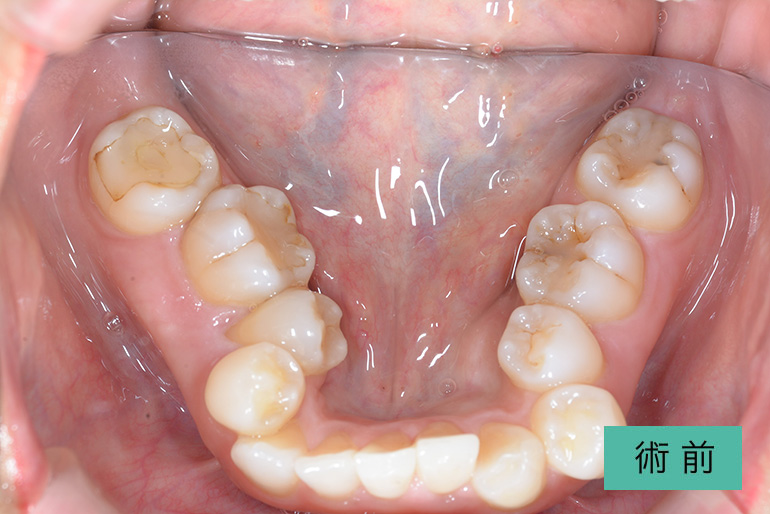

| 治療内容 | 歯並びをキレイにしたい。 口腔内容積を狭くしないように、歯列を拡大し非抜歯で矯正をする。 |

|---|---|

| 治療期間・回数 | 約3年半、40回 |

| 費用(税込) | ¥880,000(マウスピース矯正) ※自由診療 |

| リスク・副作用 | 歯肉退縮、知覚過敏、後戻り |

| 治療期間・回数 | 約6年、80回 |

| 費用(税込) | ¥880,000(マウスピース矯正) ¥620,000(セラミッククラウン) ※自由診療 |